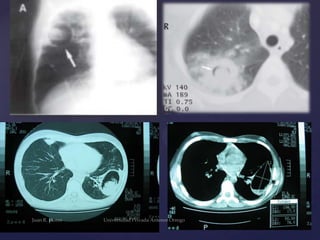

Espectro radiológico de la

infección por Aspergillus

DATOS

RADIOLOGICOS

Colonizante

Invasiva

Alérgica

•Masa sólida, redonda u oval

•Localizada en los lóbulos superiores, adyacente a la

pleura, y separada de la pared de la cavidad por un

espacio aéreo

•Forma y tamaño variable.

•Consolidaciones lobulares, segmentarias o

subsegmentarias, habitualmente múltiples

•Bronquiectasias en fases iniciales

•Opacidades tubulares multifocales relacionadas

con áreas de atelectasia e impactación mucoide.